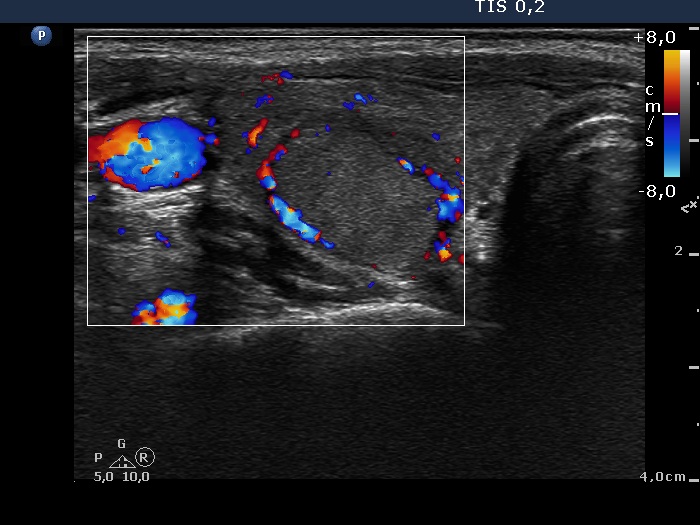

Right lobe, longitudinal scan

Right lobe, transverse scan, color Doppler mode. The lesion presents perinodular blood flow.